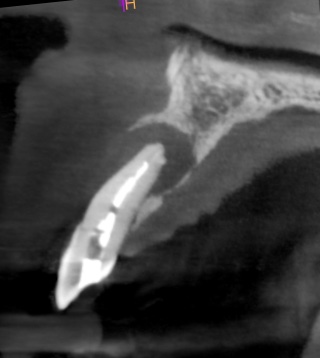

Healing was uneventful and following a seven-month maturation period, a CBCT scan confirmed the presence of the MinerOss®/autogenous bone graft and a favourable volume of bone. However, it was noted that the soft tissues covering the bone graft were thin with an absence of interdental papillae. It was determined that a connective tissue graft would be required as part of the next surgical procedure to improve the soft tissue volume and lead to the creation of papillae during the prosthetic stages.

Healing was uneventful and following a seven-month maturation period, a CBCT scan confirmed the presence of the MinerOss/autogenous bone graft and a favourable volume of bone.

The second surgery involved a palatal crestal incision and a full thickness flap elevation revealing good turnover of bone graft into host bone. A bone level implant was placed in an appropriate three-dimensional position completely surrounded by new bone and no additional bone grafting was required. A 4mm healing cap was placed.